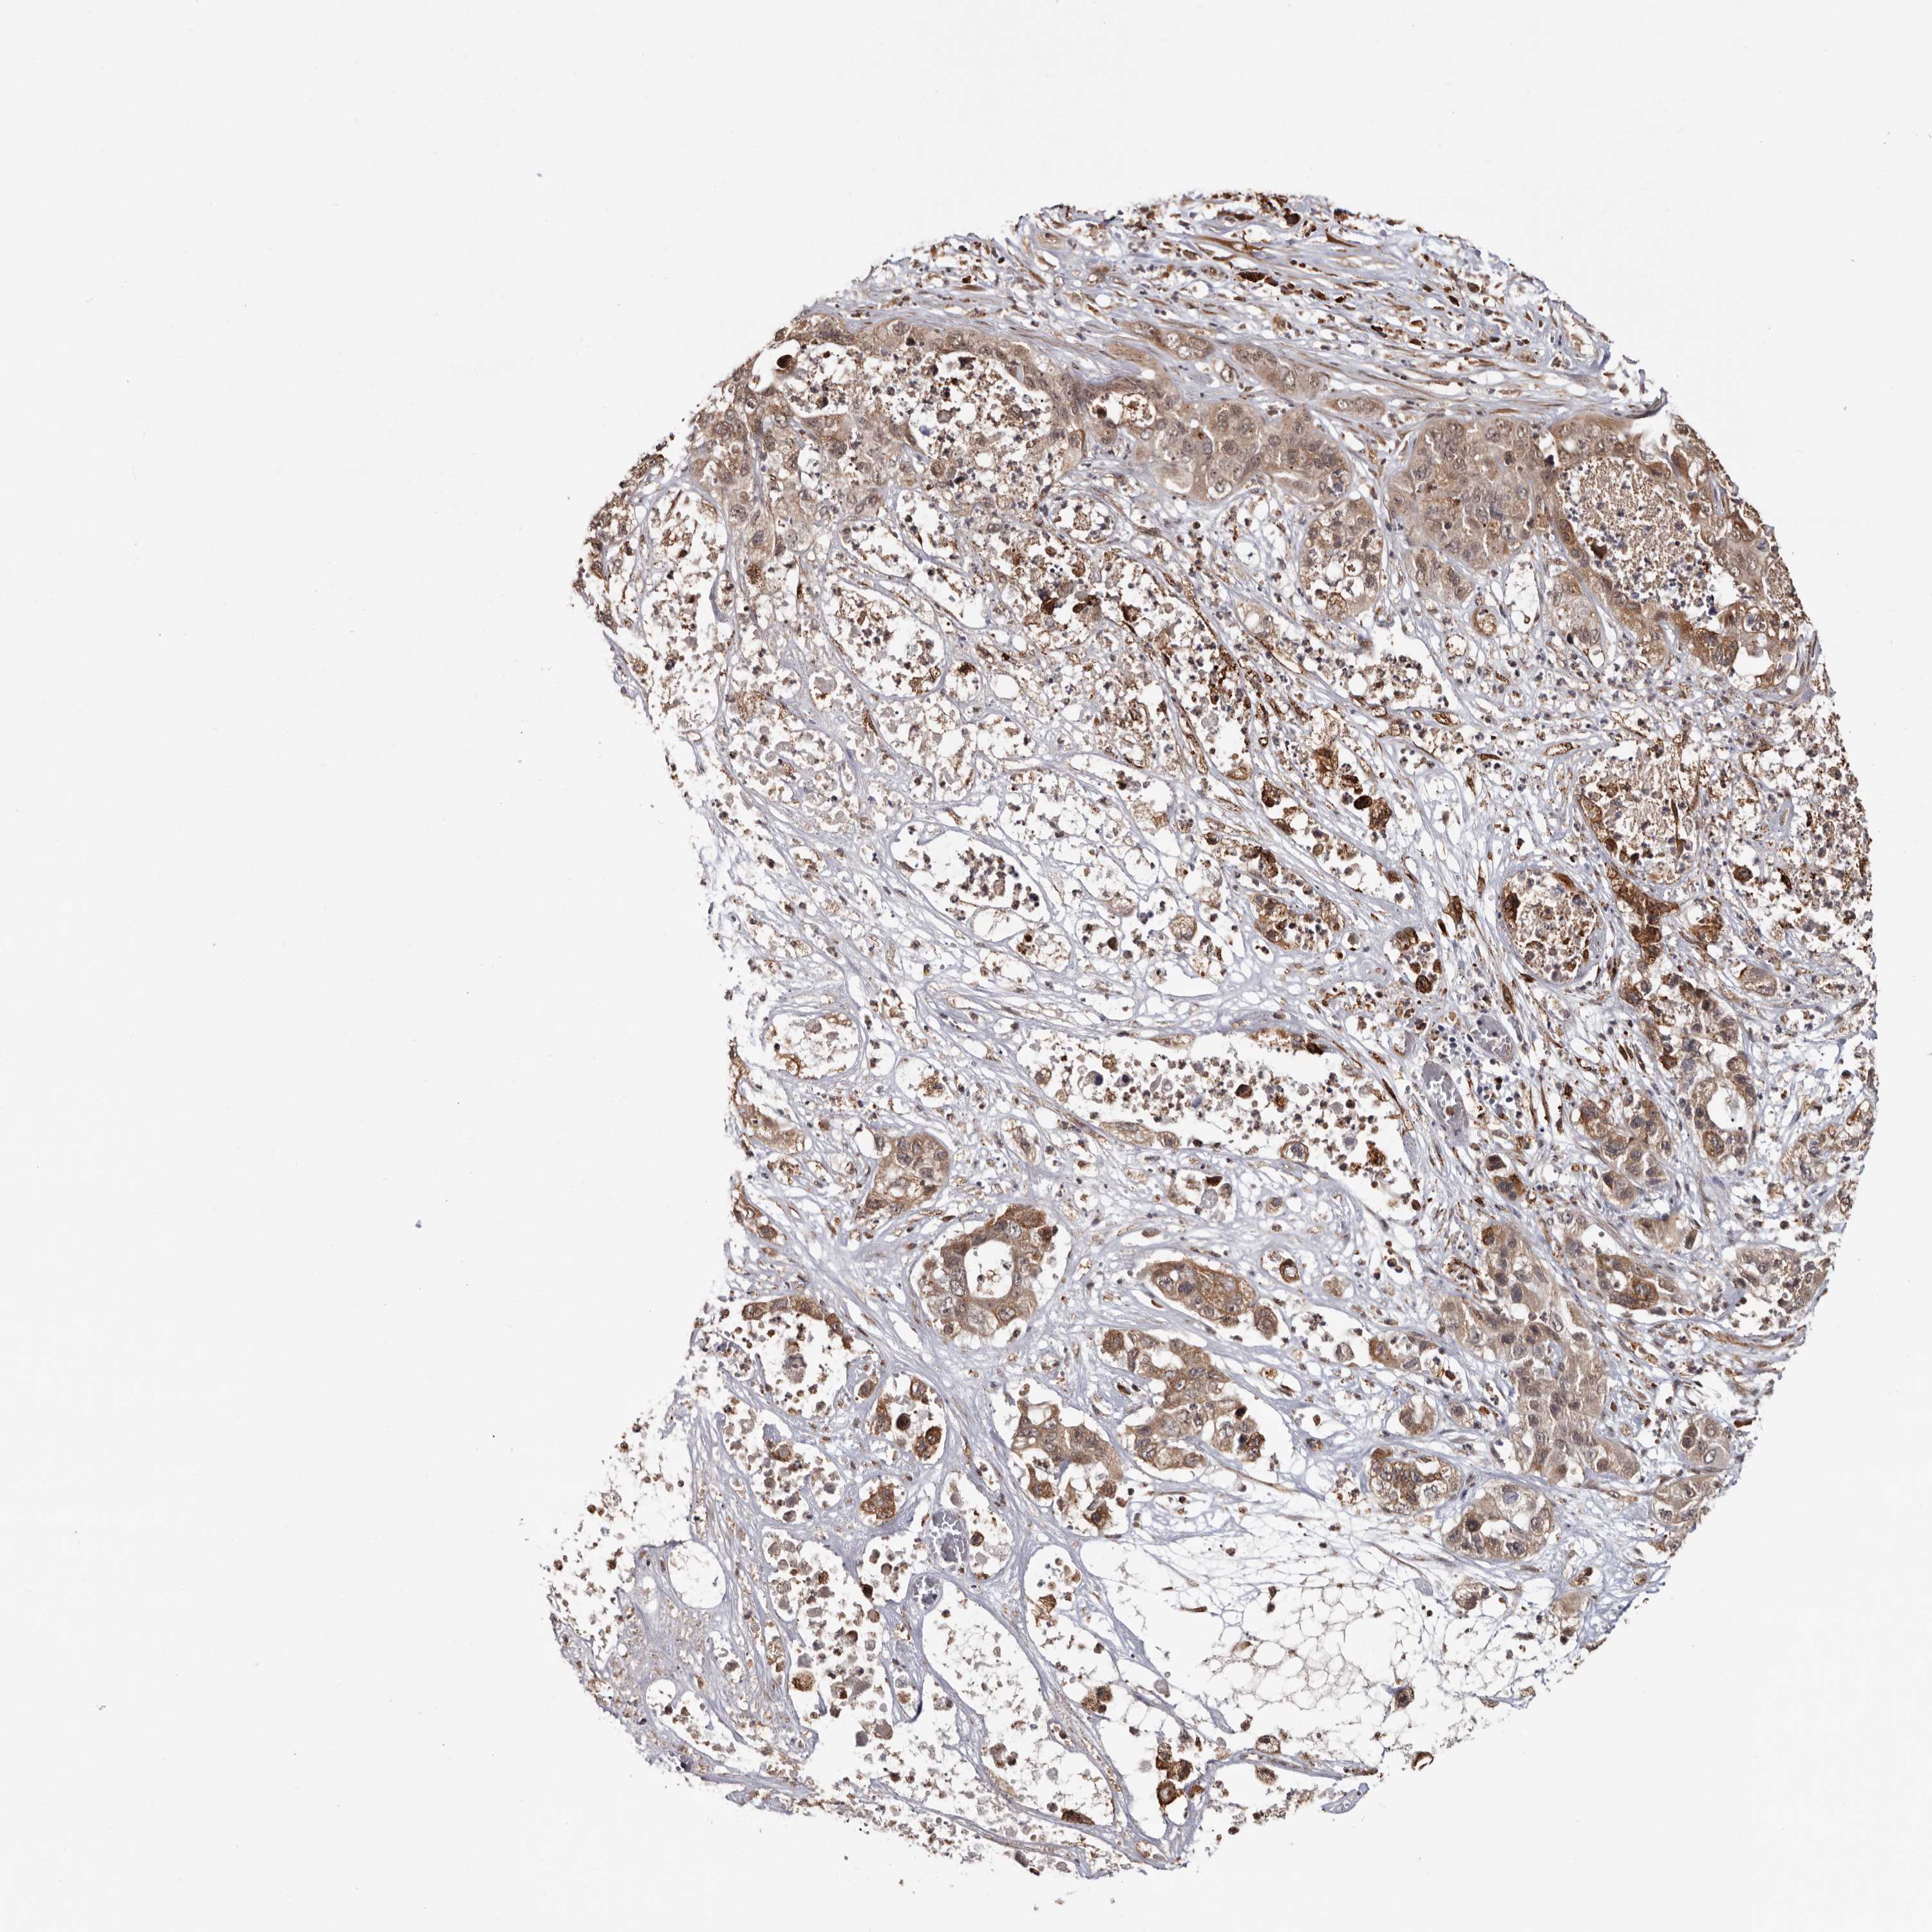

PANCREATIC CANCER - Protein expressioni

A mouse-over function shows sample information and annotation data. Click on an image to view it in a full screen mode. Samples can be filtered based on level of antibody staining by selecting one or several of the following categories: high, medium, low and not detected. The assay and annotation is described here.

Note that samples used for immunohistochemistry by the Human Protein Atlas do not correspond to samples in the TCGA dataset.

Antibody stainingi

Antibody staining in the annotated cell types in the current human tissue is reported as not detected, low, medium, or high, based on conventional immunohistochemistry profiling in selected tissues. This score is based on the combination of the staining intensity and fraction of stained cells.

Each image is clickable and will lead to virtual microscopy that enables deeper exploration of all samples and also displays staining intensity scores, fraction scores and subcellular localization as well as patient and tissue information for each sample.

Antibody HPA025970

Staining

High

Medium

Low

Not detected

Intensity

Strong

Moderate

Weak

Negative

Quantity

>75%

75%-25%

<25%

None

Location

Nuclear

Cytoplasmic/membranous

Cytoplasmic/membranous,nuclear

Adenocarcinoma, NOS